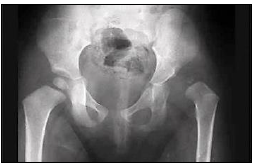

Considere uma criança com sinal de Trendelemburg positivo e a seguinte radiografia com quadril:

Enunciado 901589-1

É correto afirmar que trata-se de